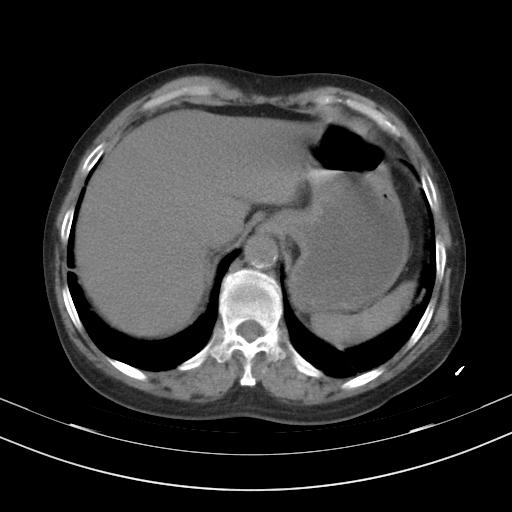

老年女性,嗜睡3天,意识模糊。轻咳,无发热。

两肺慢支炎伴感染,左侧胸腔积液。纵膈及双侧肺门淋巴结肿大建议复查。

双肺多发淡片影,毛玻璃影,,支持支气管肺炎,,建议血气找原因,,嗜睡是否肺性脑病?有没有慢支病史?

双肺炎症,建议抗炎治疗后复查,见过几个老年肺炎病例,没有发烧、咳嗽症状,直接以昏迷就诊。

1)两肺感染性病变;建议抗炎治疗后复查。2)纵隔淋巴结肿大。3)左侧胸腔积液。